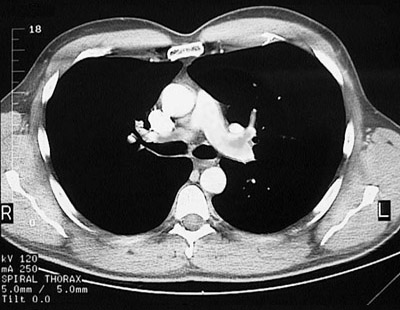

Figure 1: Chest CT scan

Doris develops the sudden onset of chest pain with diaphoresis and shortness of breath late one afternoon. She is taken to the emergency department of a local hospital.

On obtaining a history she states that she has had occasional episodes of chest pain in the past 5 years, but nothing this bad, particularly because of the shortness of breath. She had some chest pain about a week ago. She has smoked 1 pack of cigarettes per day for the past 45 years.

On examination she is in moderate distress. Vital signs show temperature 36.9 C, pulse 101/min, respiratory rate 25/min, and blood pressure 145/95 mm Hg. Her lungs are clear to auscultation. Her heart rate is slightly irregular; there are no murmurs. Her abdominal exam is normal. Pulses are 2+ and equal in all extremities. She has tenderness to palpation of her upper posterior right leg. She has no neurologic findings.